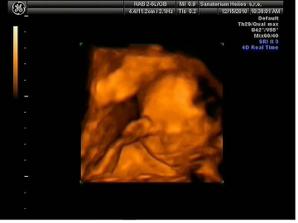

Kvůli sněhu jsme skoro nestihli ten velký UTZ☹ale tatínek navzdory sněhové kalamitě šlápl na plyn a s nepatrným zpožděním už jsme koukali na svého potomka, všechno je v pořádku, mimi je krásné, zdravé a vypadá to na Terezku....maminka s tatínkem jsou moc šťastní....

15.12. 3D utz, maminka má placentu na přední stěně, takže mimi je s ní zakryté🙂 a opravdu je to Terezka!!!!! Ale má nemocnou nožku přesněji Pes Equinovarus Congenitus , zní to hůř než to vypadá, v pondělí budeme vědět víc...no maminku to trošku rozplakalo...ale bude to OK, určitě!!!!